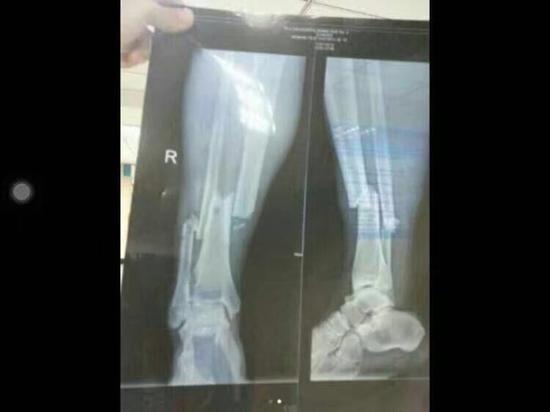

作为职业球员,孙祥肯定不会故意去踢断对手的腿,但从整个动作以及慢动作来分析登巴巴的受伤,孙祥属于很典型的暴力“不合理冲撞“导致了对手的受伤并且骨折:比赛进行到第63分钟,孙祥和登巴巴同时去抢一个足球的控制权,当时两人实际上都没有碰到皮球,于是登巴巴加速去追球,但孙祥出于防守卡位的目的,用了一个身体冲撞的动作,这次身体接触在足球场上也算是司空见惯,但悲催的结果是,由于登巴巴被孙祥的肩部顶撞导致身体失去重心,身体倒地之前左脚支撑腿正好碰上孙祥往下踩地的左腿,于是在高速运动中登巴巴被孙祥“黑了”一脚导致了严重的后果,左脚支撑腿的胫腓骨全部骨折,断腿悲剧在中超联赛里又一次发生。

照片看得让人胆寒!